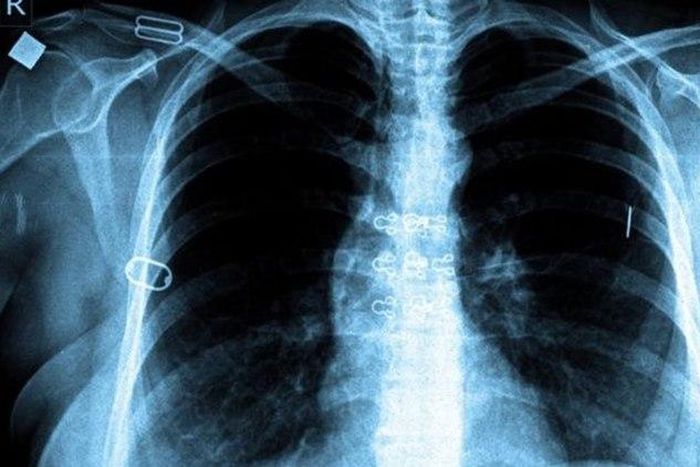

Fight against Tuberculosis paying off globally, report says

The World Health Organisation (WHO)has said that the fight against tuberculosis (TB) is paying off, with this year’s death rate nearly half of what it was in 1990.

This is according to WHO’s Global Tuberculosis Report 2015, which was released on Wednesday in Washington D.C.